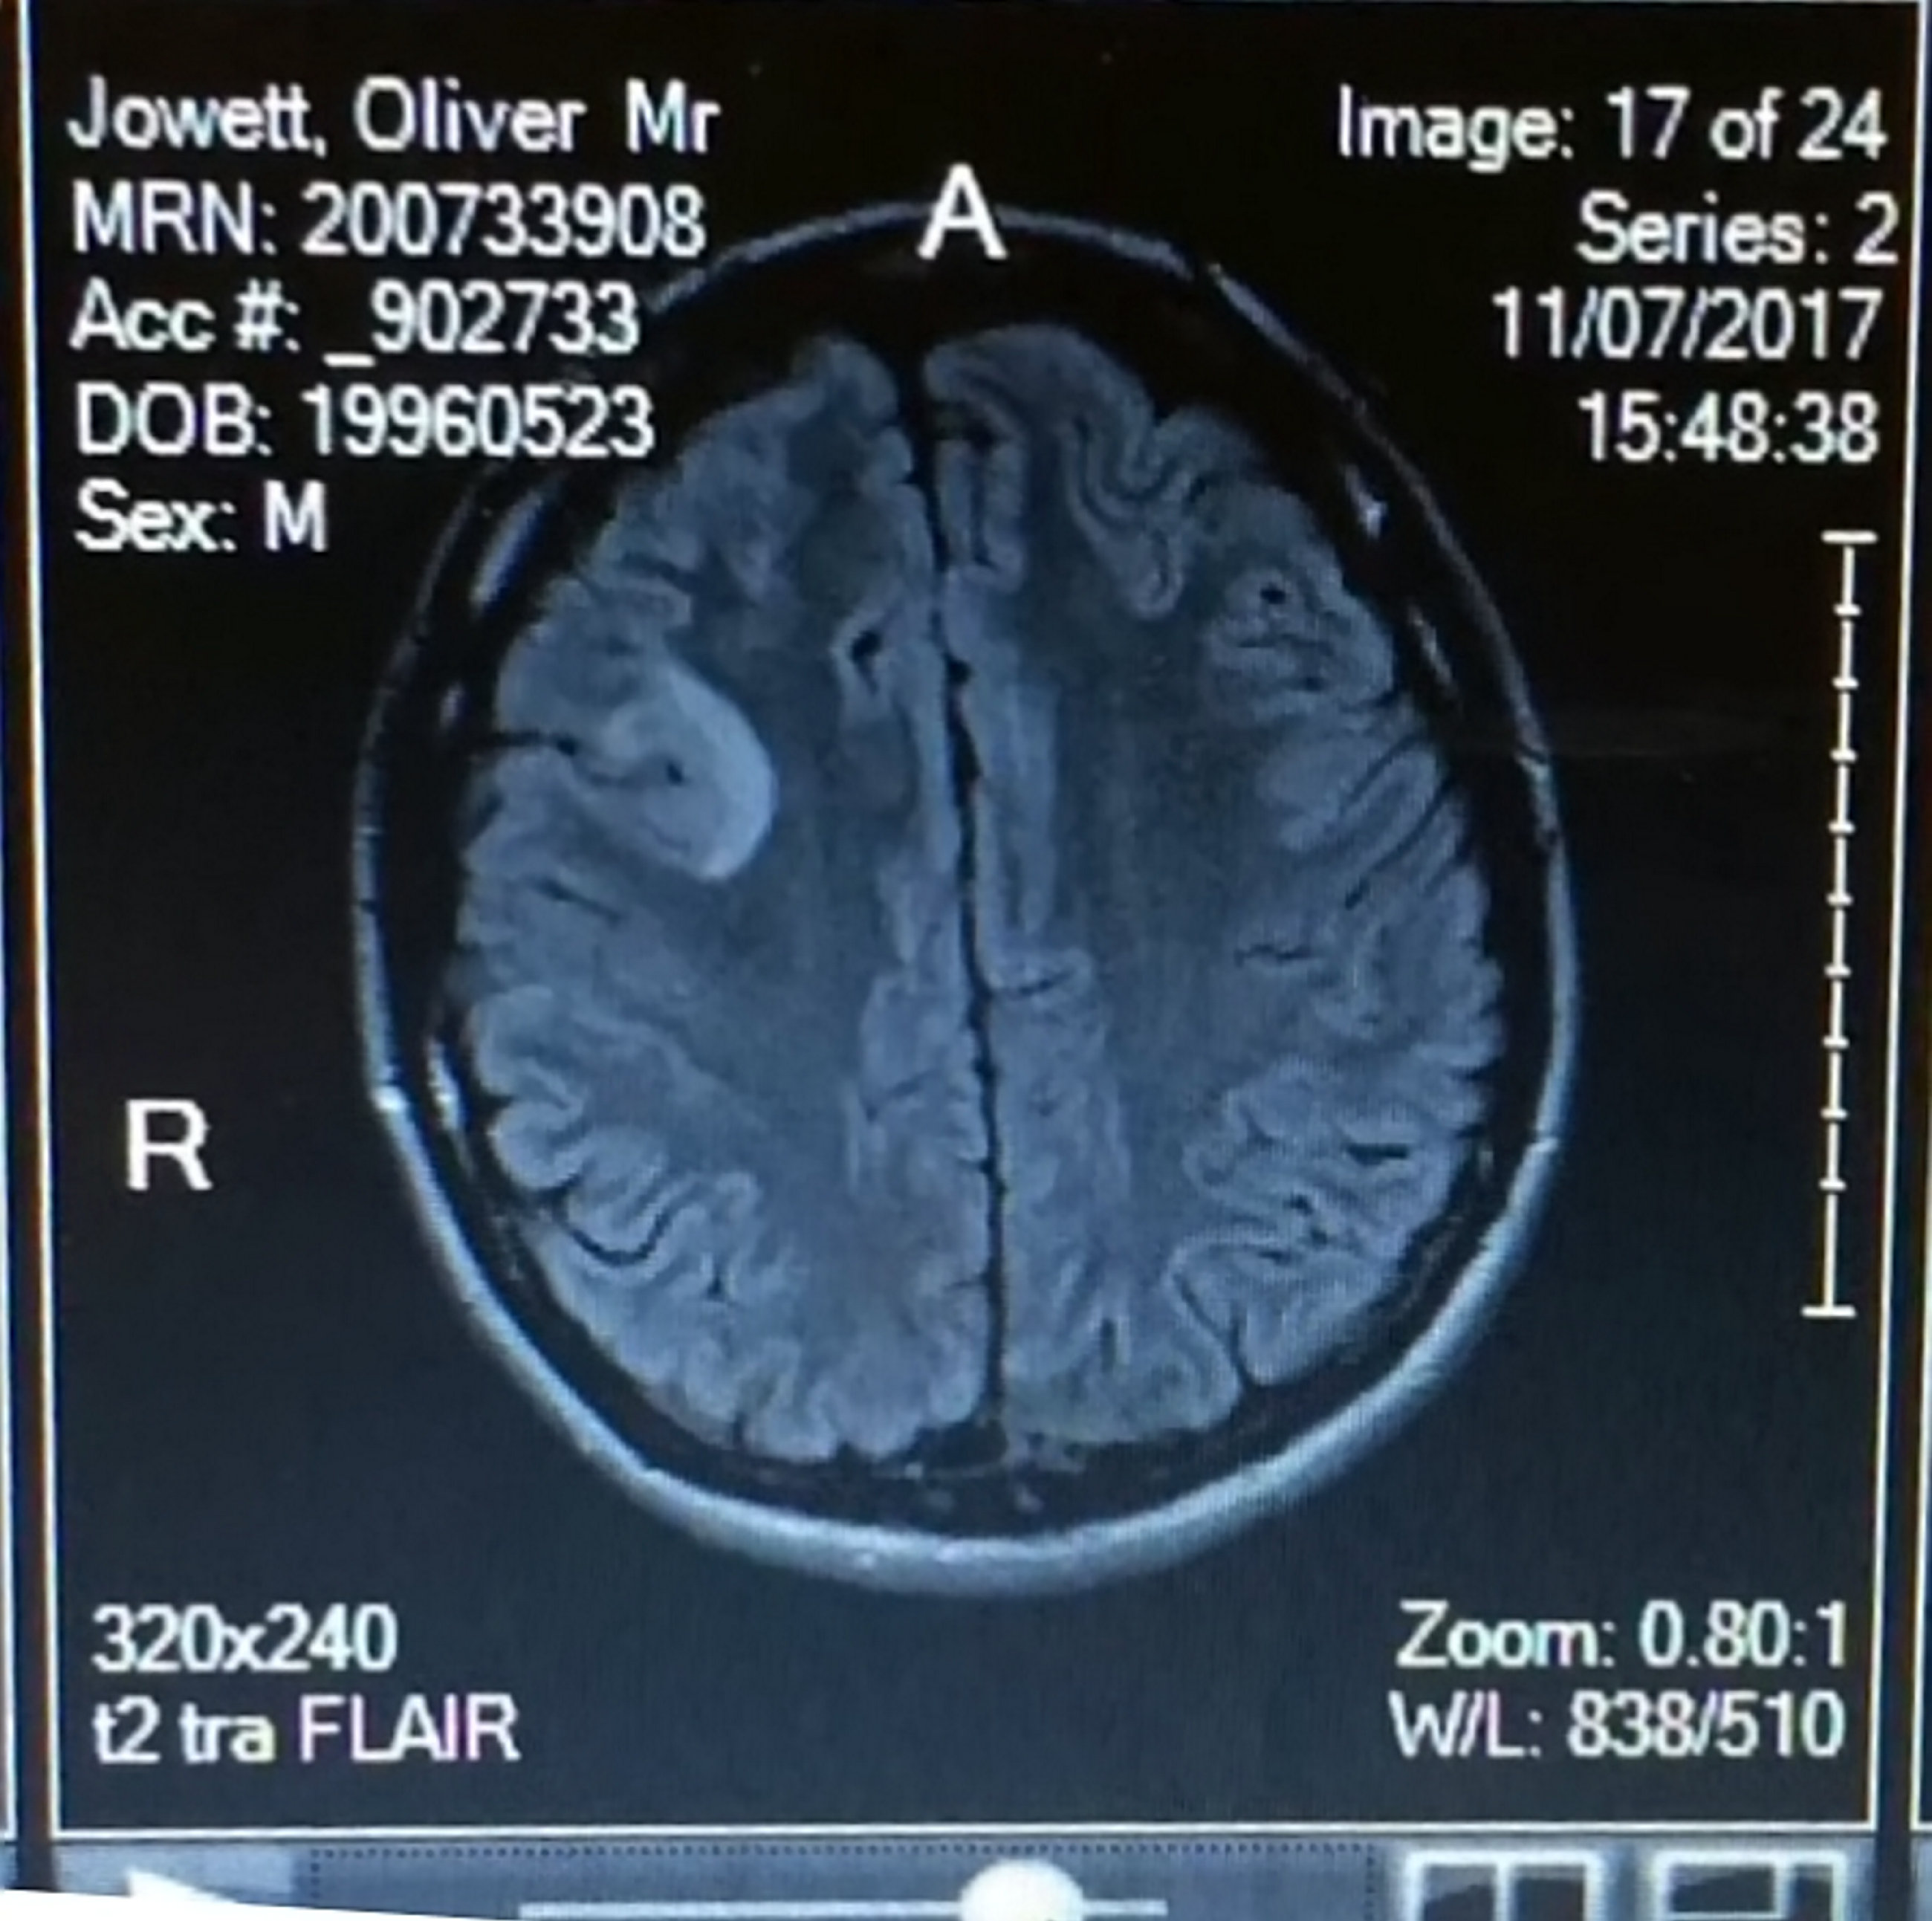

Body transformation in just 12 weeks is very impressive for anyone, but for 22-year-old Ollie Jowett it was an amazing feat as he was also suffering from a cancerous brain tumor.

Ollie is originally from Cornwall but moved to Belfast for his job as a personal trainer, but the 22-year-old’s life took an unfortunate turn when he was diagnosed with a malignant brain tumor.